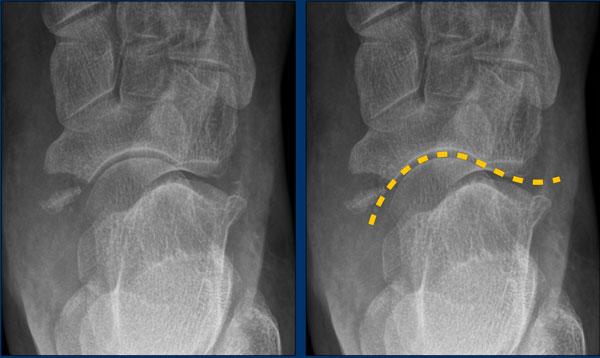

case 2 – chronic pain post ankle sprains

The findings are:

- mỏm trước xương gót kéo dài khớp với xương thuyền.

- the diagnosis is calcaneonavicular coalition.

Xương gót và xương thuyền thường không khớp với nhau.

Trong trường hợp liên kết xương, có thể thấy một cầu xương nối liền hai xương này.

Compare to the normal situation.

Với liên kết xơ hoặc sụn, các xương nằm gần nhau, cả hai đều có bề mặt không đều, và phần trước trong của xương gót bất thường bị giãn rộng hoặc phẳng dẹt.

Trên phim X-quang tư thế bên, sự kéo dài của phần lưng trước xương gót có thể mô phỏng hình ảnh mũi con thú ăn kiến.

Thiểu sản xương sên đôi khi được quan sát thấy trong liên kết gót-thuyền.

Trên CT, chúng ta thấy sự hợp nhất giữa xương gót và xương thuyền.

CT cho thấy xơ cứng xương và các nang dưới sụn như là dấu hiệu của ‘ma sát’ do khớp tân tạo.

MRI cho thấy phù tủy xương như là dấu hiệu của sự hợp nhất có triệu chứng.